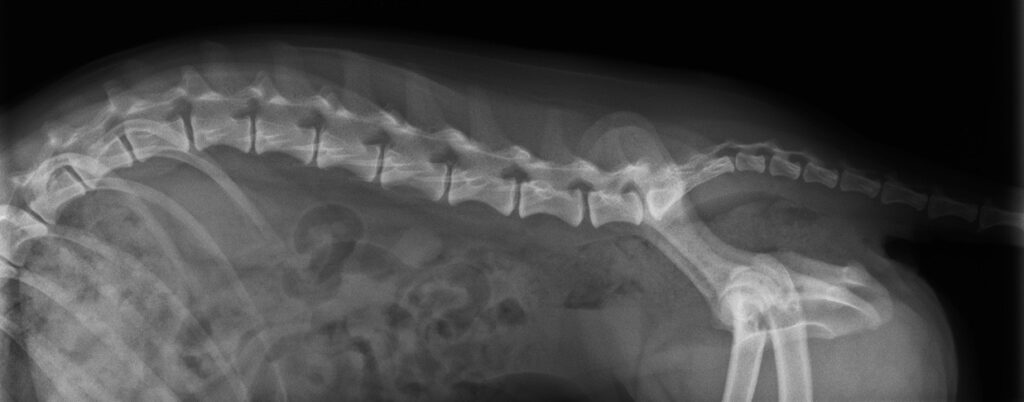

まずは触診(神経学的検査)とレントゲン検査を行いました。

レントゲン検査では、脊椎の湾曲が認められるものの、明らかな骨病変、椎間板病変は認められませんでした。

レントゲン検査では脊椎の湾曲はあるものの、明らかな病変は認められませんでした。